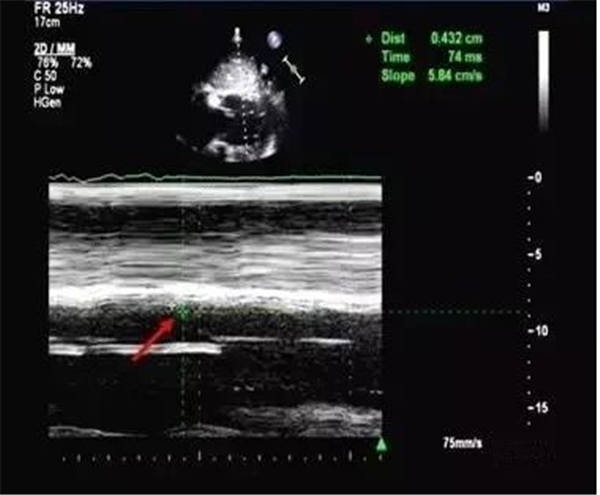

肺動脈前向血流頻譜收縮中期出現切跡,同時伴隨血流速度明顯減低、血流加速時間(ACT)縮短(<80 ms)、右室射血前期(RPEP)縮短(<300 ms)及ACT與右室射血時間(RVET)比值減低(<40%)等,即常說的“指拳征”。